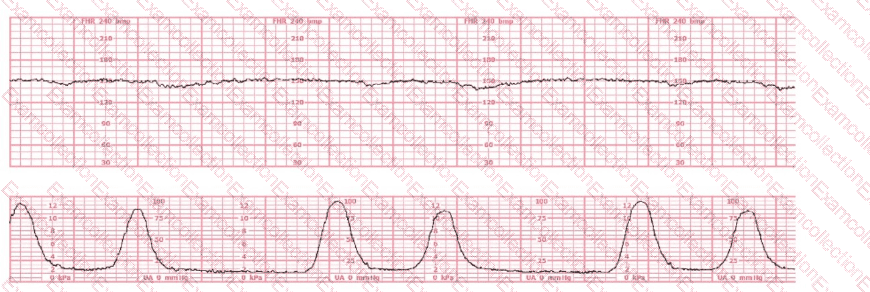

This fetal heart rate tracing represents: